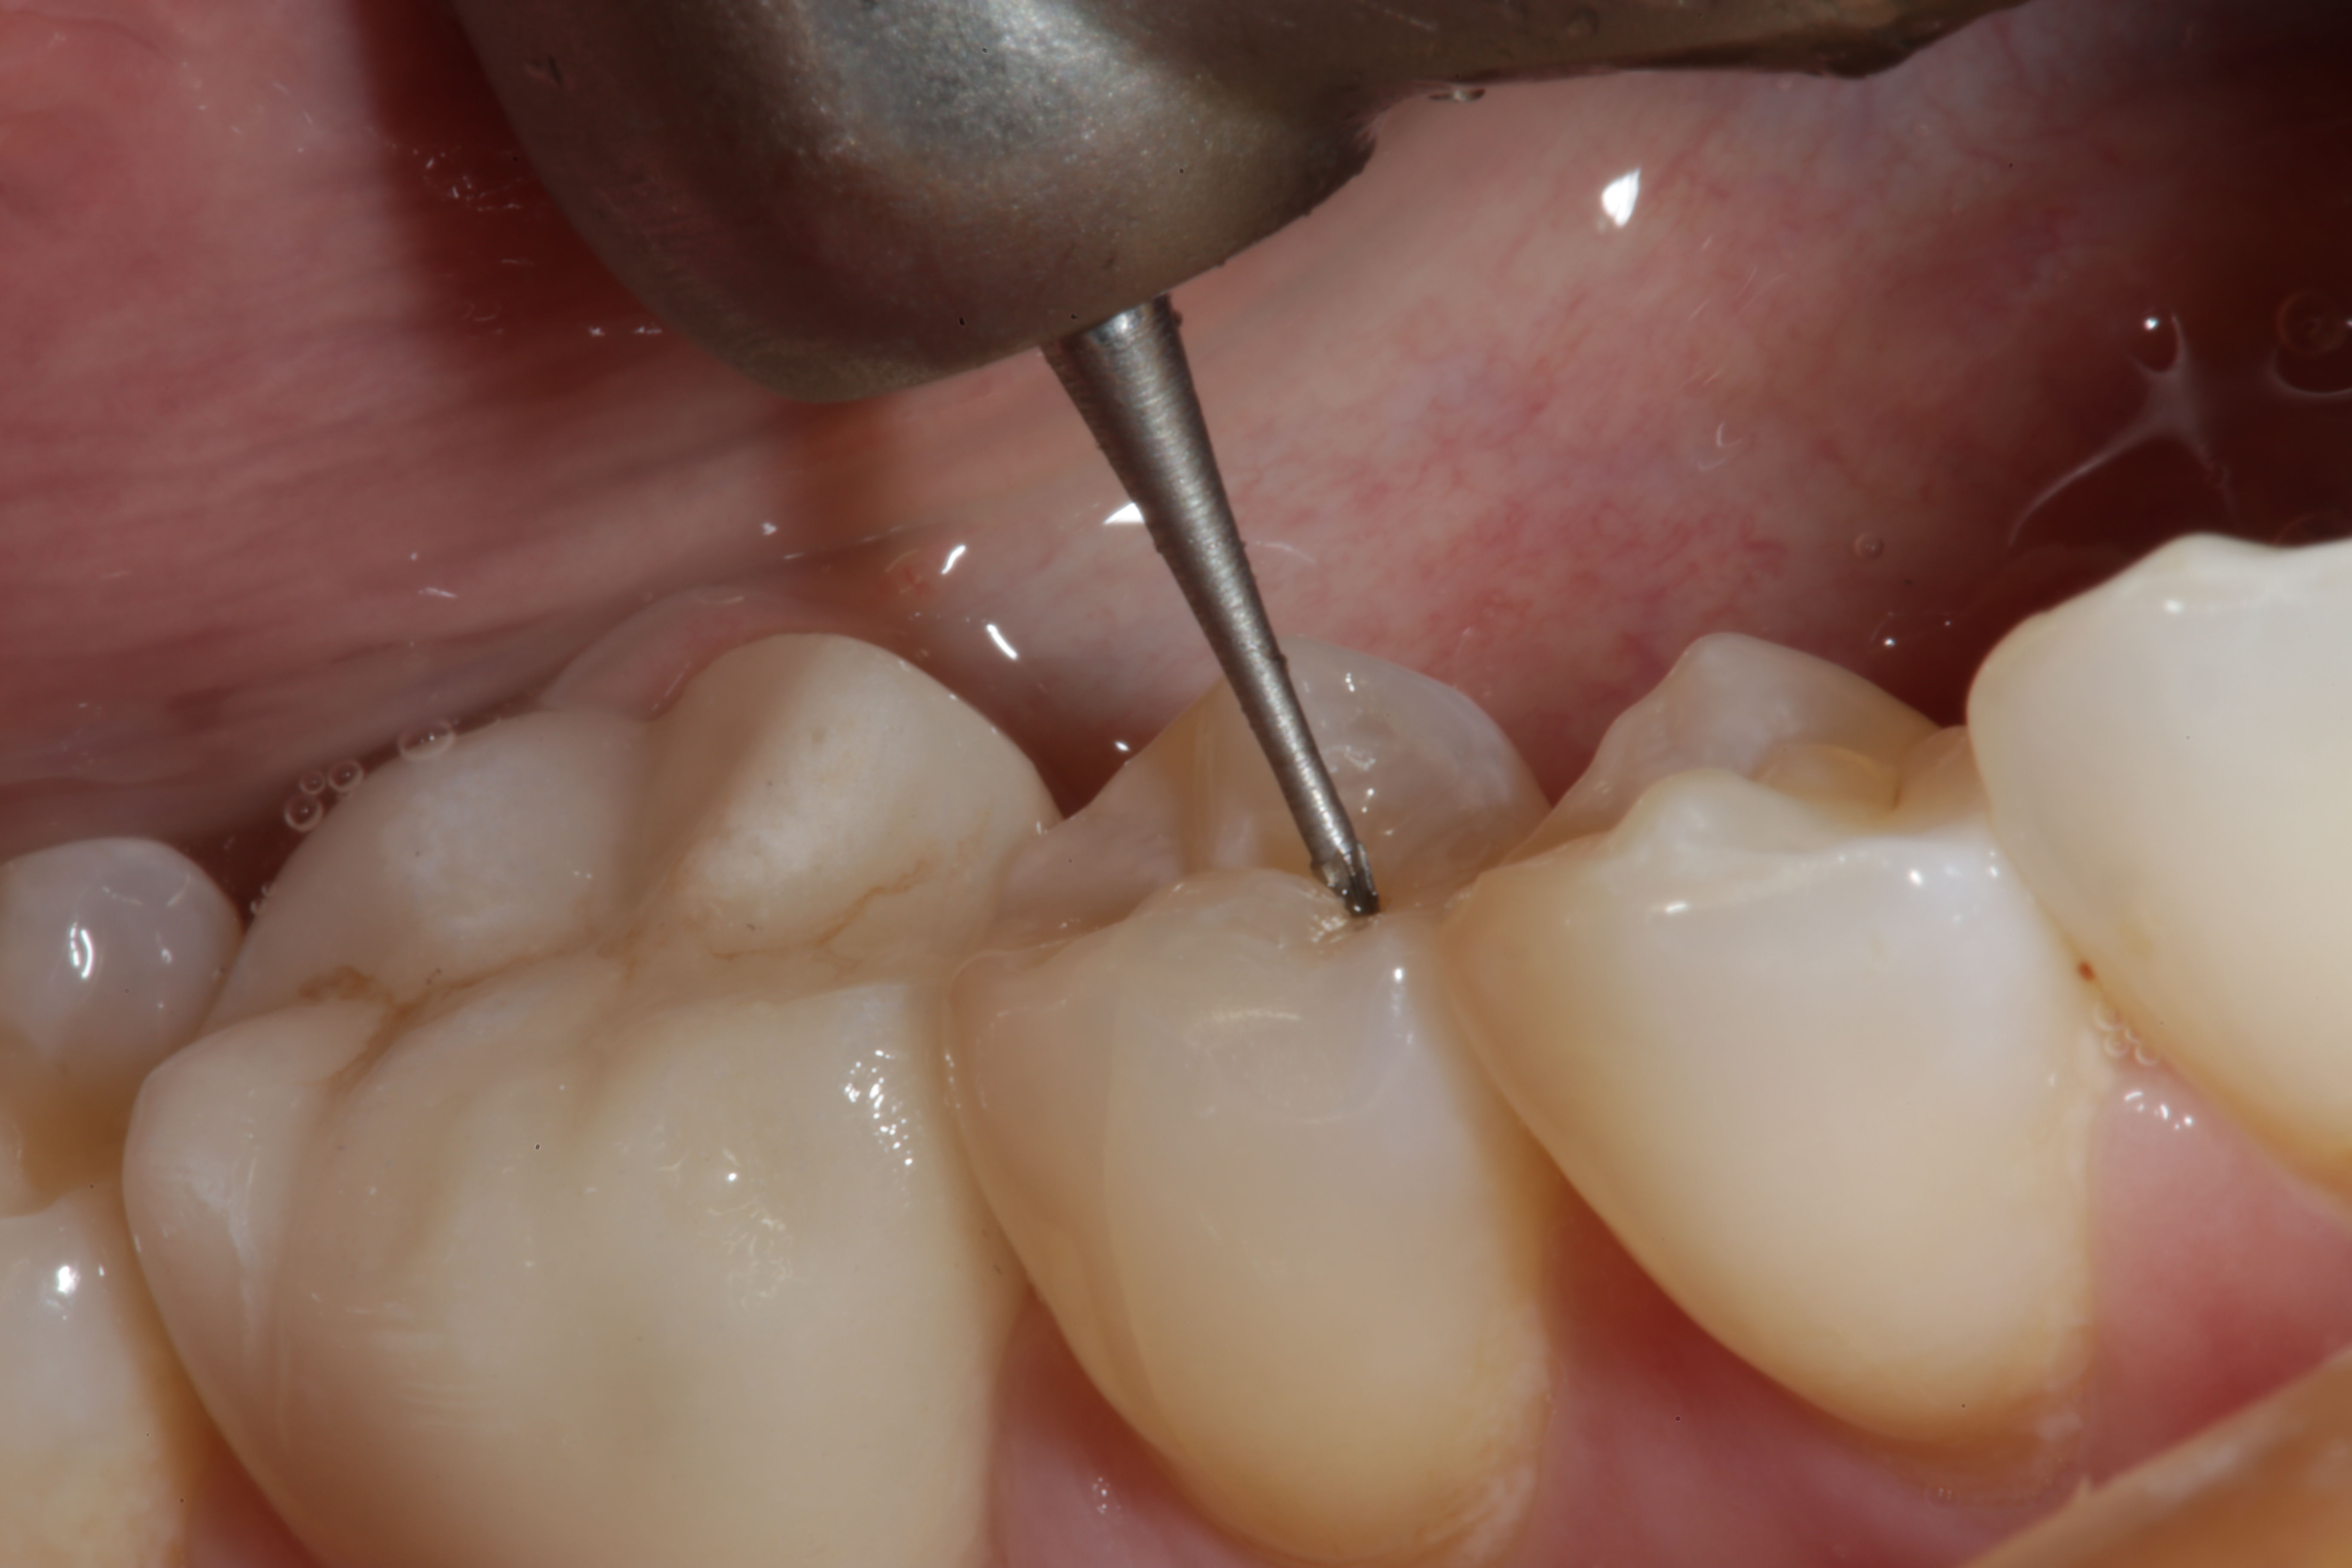

Fig 3. A heavy-bodied Giomer flowable composite is used to restore the preparation made in tooth No. 29.

Figure 3